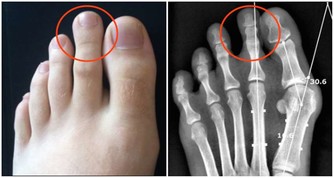

*****3.置換類的手術*****

有時需要換肝這種高難度的手術,手術過程複雜多樣,

在做這種手術時,對於病人來說需要開胸,自己衣服上可能攜帶一些病菌,在手術過程中造成不必要的影響,